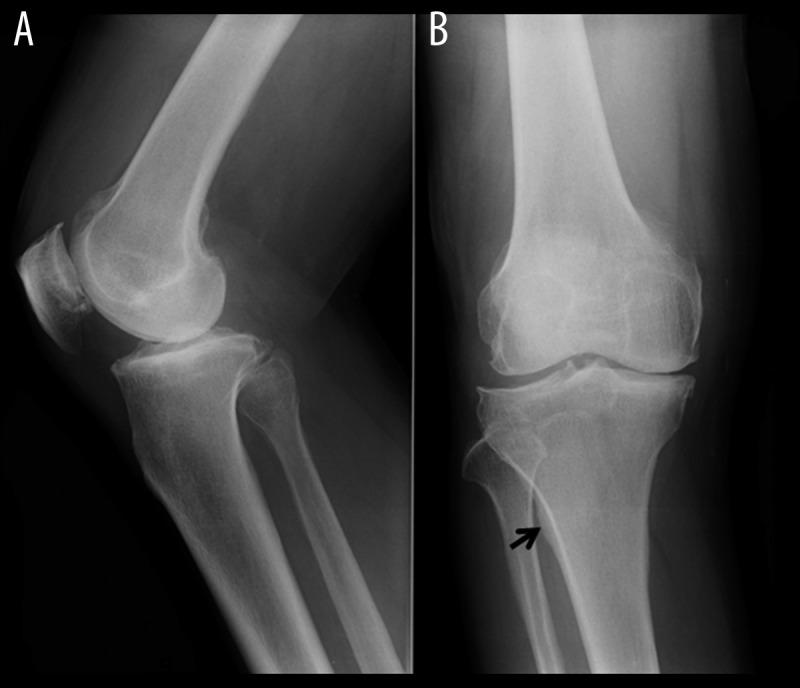

Knee joint pain potentially due to bone alterations in a knee osteoarthritis patient.

Plain radiographs and MRI examinations performed during follow-up suggested that the pathophysiology of the patient's knee OA and joint pain may have been primarily due to bone alterations.